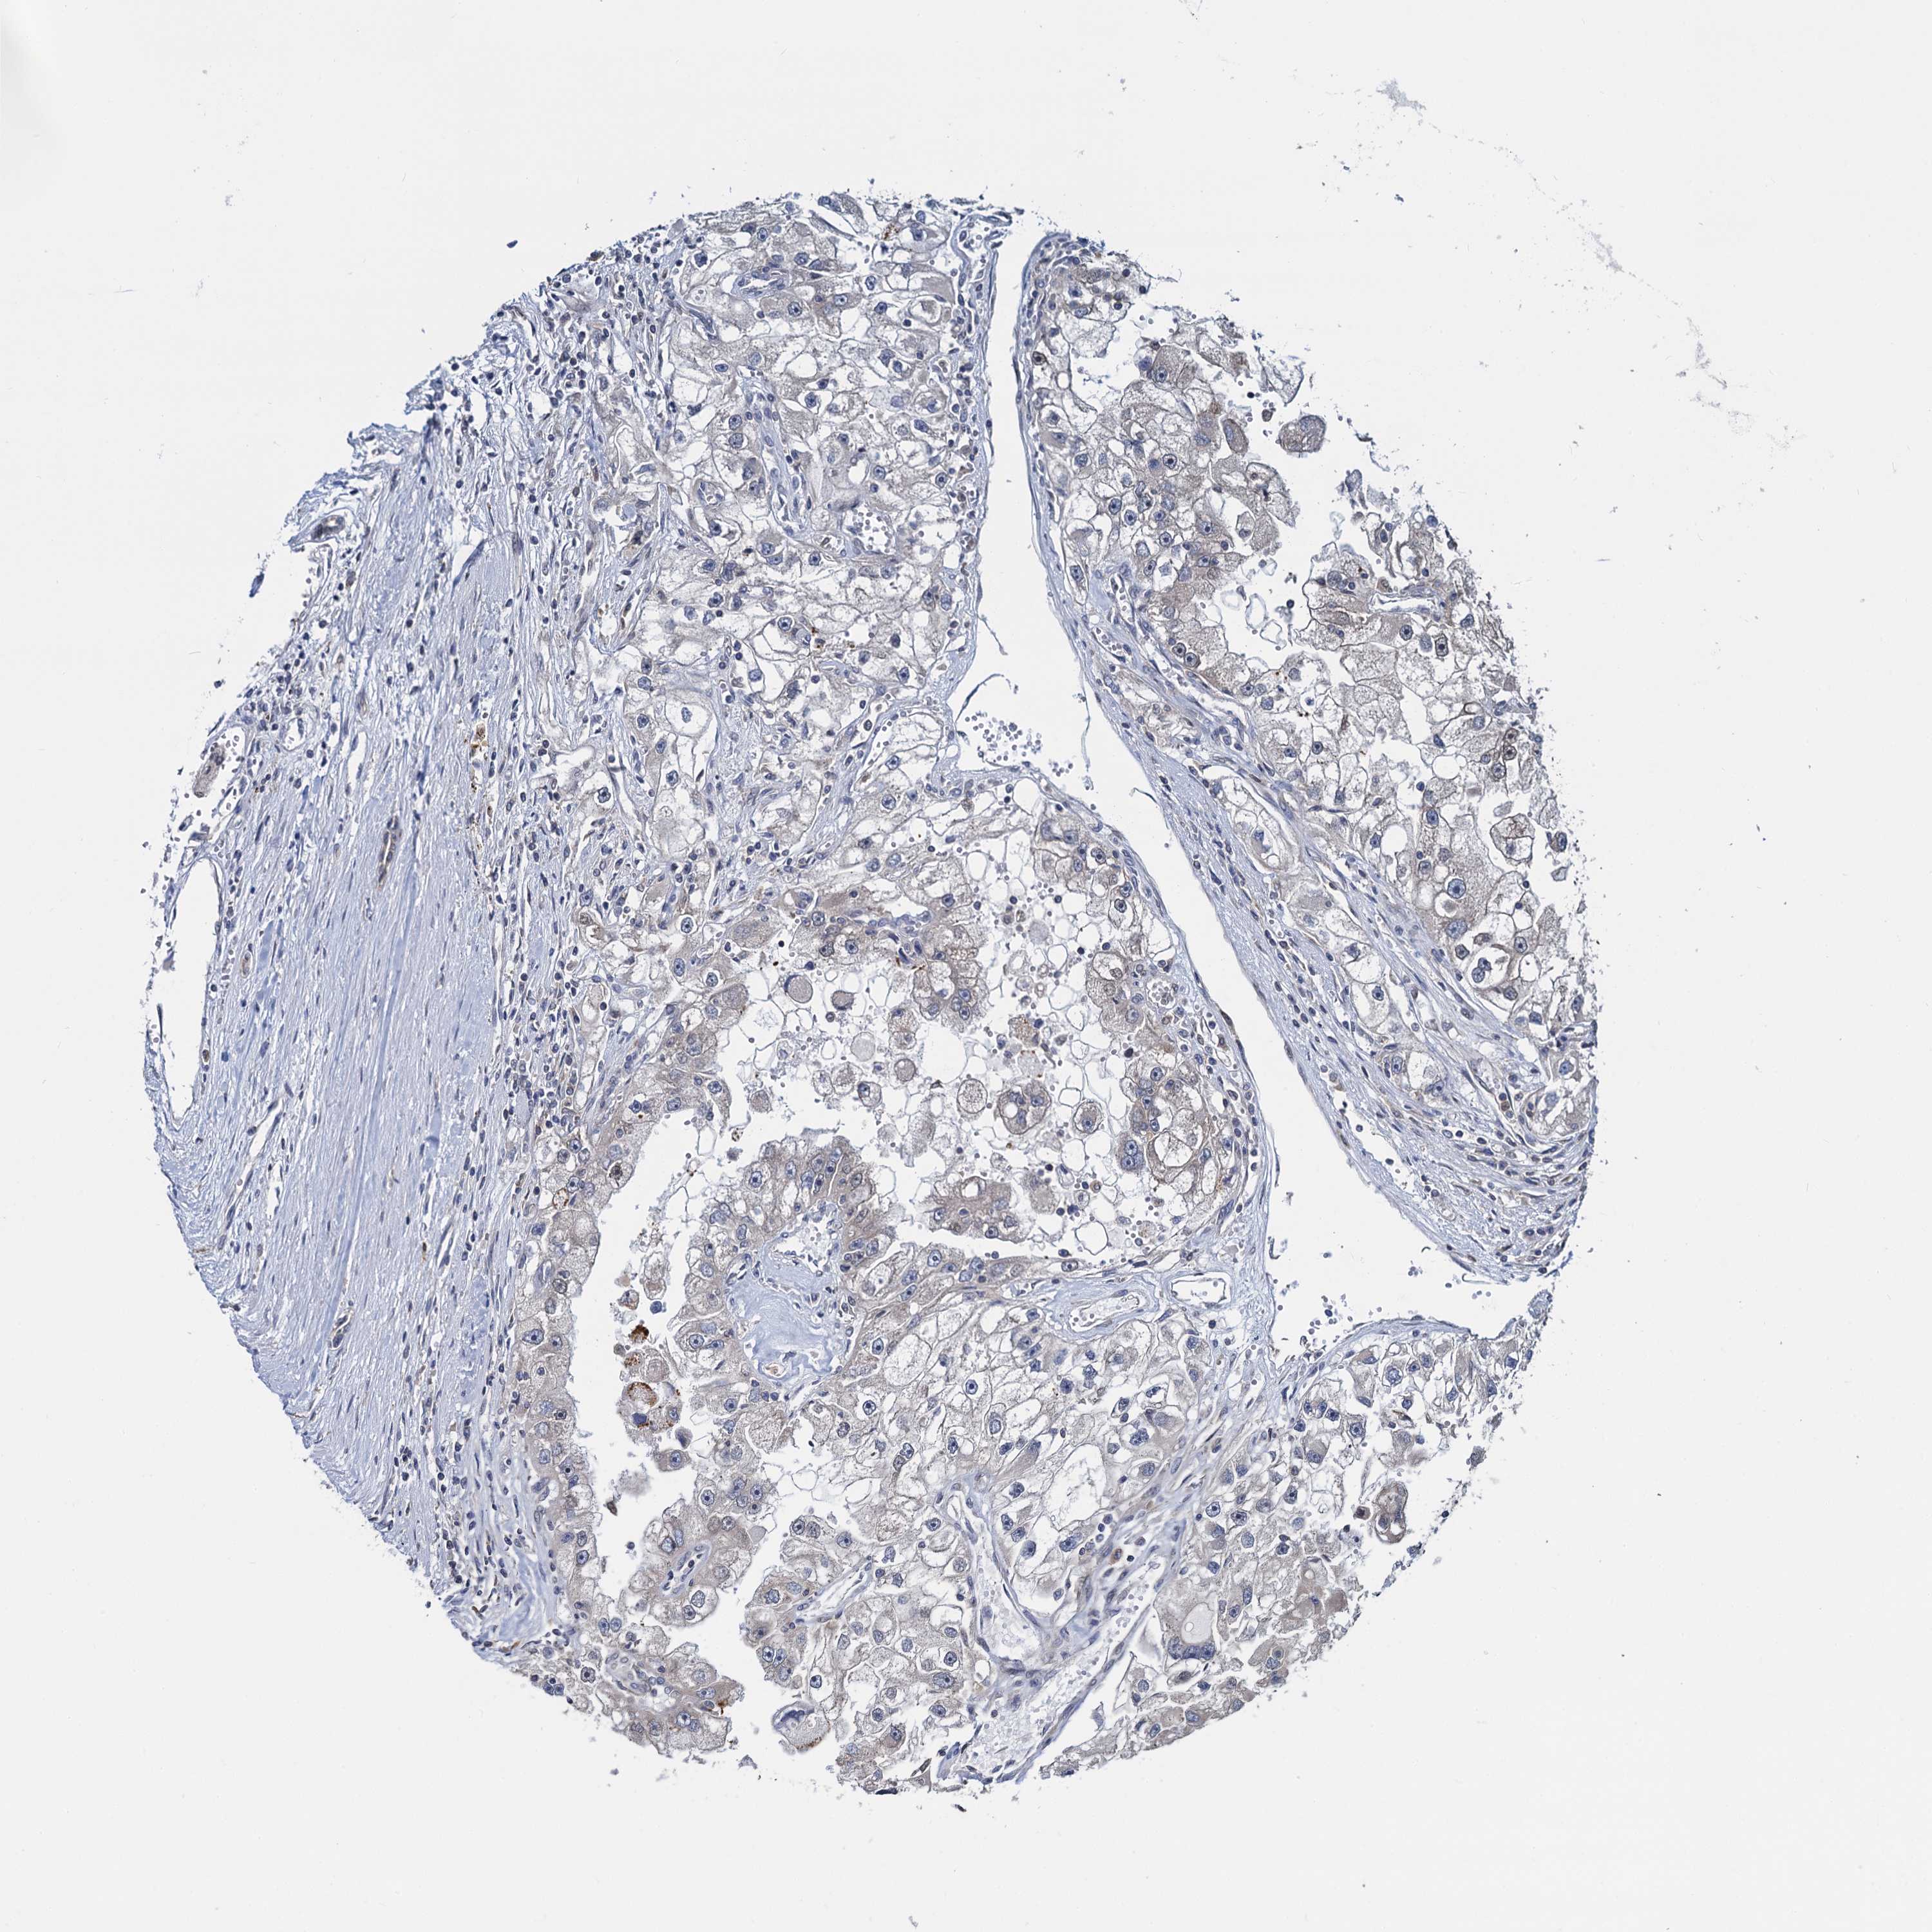

KIDNEY RENAL CLEAR CELL CARCINOMA (TCGA) - Interactive survival scatter ploti

The Survival Scatter plot shows the clinical status (i.e. dead or alive) for all individuals in the patient cohort, based on the same data that underlies the corresponding Kaplan-Meier plots. Patients that are alive at last time for follow-up are shown in blue and patients who have died during the study are shown in red.

The x-axis shows the expression levels (FPKM) of the investigated gene in the tumor tissue at the time of diagnosis. The y-axis shows the follow-up time after diagnosis (years). Both axes are complimented with kernel density curves demonstrating the data density over the axes. The top density plot shows the expression levels (FPKM) distribution among dead (red) and alive patients (blue). The right density plot shows the data density of the survived years of dead patients with high and low expression levels respectively, stratified using the cutoff indicated by the vertical dashed line through the Survival Scatter plot. This cutoff is automatically defined based on the FPKM cutoff that minimizes the p-score. The cutoff can be changed by dragging the vertical line or by entering a cutoff value in the square labeled "Current cut-off".

Under the Survival Scatter plot the p-score landscape (black curve; left axis) is shown together with dead median separation (red curve; right axis). Dead median separation is the difference in median mRNA expression between patients who have died with high and low expression, respectively. It is calculated as follows: median FPKM expression of dead patients with high expression - median FPKM expression of dead patients with low expression. This is intended to aid the user in visually exploring custom cutoffs and the associated p-scores and dead median separation.

Individual patient data is displayed and can be filtered by clicking on one or more of the category buttons on the top of the page. Categories describing expression level and patient information include: high, low, alive, dead, female, male and tumor stages. The scale of the x-axis can be toggled between linear and log-scale by clicking on the "x log" button. Mouse-over function shows TCGA ID, patient information and mRNA expression (FPKM) for each patient.

& Survival analysisi

Kaplan-Meier plots summarize results from analysis of correlation between mRNA expression level and patient survival. Patients were divided based on level of expression into one of the two groups "low" (under cut off) or "high" (over cut off). X-axis shows time for survival (years) and y-axis shows the probability of survival, where 1.0 corresponds to 100 percent.

RNF125 is potential prognostic, high expression is favorable in Kidney Renal Clear Cell Carcinoma (TCGA)

Best expression cut offi

Based on the FPKM value of each gene, patients were classified into two groups and association between prognosis (survival) and gene expression (FPKM) was examined. The best expression cut-off refers the FPKM value that yields maximal difference with regard to survival between the two groups at the lowest log-rank P-value. Best expression cut-off was selected based on survival analysis .

When clicking on this number, the vertical dashed line indicating cut-off, the interactive survival plot, and the Kaplan-Meier curve will be adjusted to show results based on the best expression cut-off.

: 4.18

TCGA RNA samplesi

RNA-seq data is reported as average FPKM (number Fragments Per Kilobase of exon per Million reads), generated by the The Cancer Genome Atlas (TCGA) .

Normal distribution across the dataset is visualized with box plots, shown as median and 25th and 75th percentiles. Points are displayed as outliers if they are above or below 1.5 times the interquartile range. FPKM values of the individual samples are presented next to the box plot.

Average pTPM 3.2

Number of samples 521